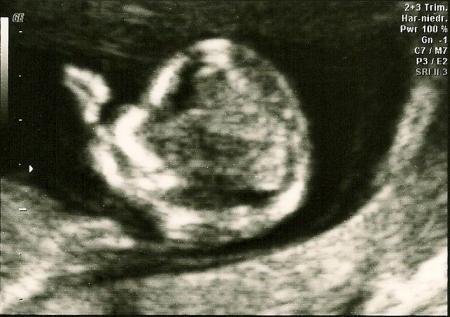

Hallo zusammen, ich wollte euch noch schnell von der NT-Messung heute berichten, bevor mein Kopf platzt. Ich habe heute tierische Kopfschmerzen. Werde wohl nachher eine Paracetamol nehmen, damit ich schlafen kann. Möglicherweise ist mein niedriger Blutdruck mit Schuld daran, keine Ahnung. Also, unsere kleine Maus lag gleich so, dass mein FA sofort die NT messen konnte. Das Ergebnis war mit 0,96 mm sehr gut (SSW 11+5). Nun muss ich noch das biochemische Ergebnis abwarten, erst dann erfahre ich natürlich das Gesamtrisiko. Trotzdem bin ich schonmal froh, dass die Nackenfalte unauffällig ist. Nachdem meine letzte Schwangerschaft bei der NT-Messung (unfreiwillig) endete, ist mir nun schon ein großer Stein vom Herzen gefallen. Ich hoffe, das Gesamtergebnis bekomme ich Anfang nächster Woche. LG

Hier noch die Bilder...